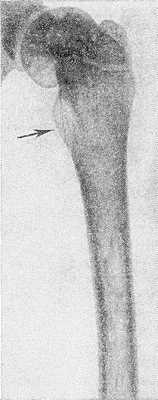

Рис. 4. Рентгенограмма бедра ребенка 10 лет при болезни Гоше: выражено утолщение шейки бедренной кости (указано стрелкой).

Наиболее часто изменения обнаруживают в длинных трубчатых костях и позвоночнике. Первое место по частоте поражения занимает дистальная половина бедра, где выявляют характерное веретенообразное или булавовидное вздутие кости (рис. 2 и 3) с истончением коркового слоя, к-рое часто сочетается с грубоячеистой структурой, внутрикостными обызвествлениями, отдельными очагами деструкции и иногда с эностальным склерозом кости. Периостозы, как правило, не развиваются; иногда могут наблюдаться обширные краевые деструкции, сопровождающиеся периостозами. В головке бедренной кости образуются асептические некрозы по типу болезни Пертеса со свойственной данному заболеванию стадийностью процесса и исходами (см. Пертеса болезнь). Может наблюдаться утолщение шейки бедра (рис. 4) с образованием coxa vara.